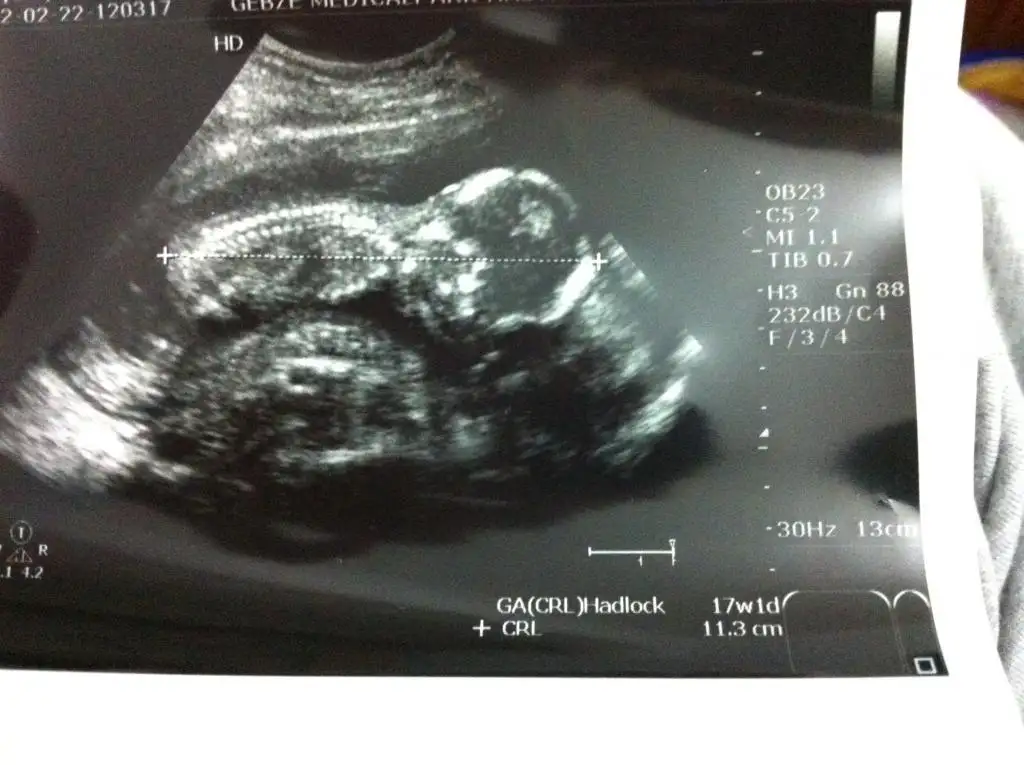

canım az iğne kullacağım öyle miOOY OY MAŞALLAH YESİNLERÇOK GÜZEL ALLAH SAĞLIKLA KUCAĞINA ALDIRSIN.....

OOY OY MAŞALLAH YESİNLERÇOK GÜZEL ALLAH SAĞLIKLA KUCAĞINA ALDIRSIN.....